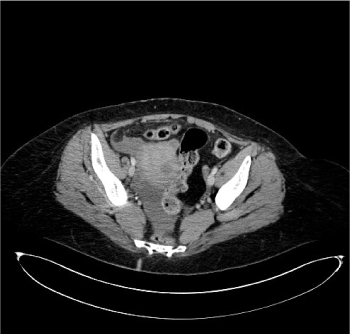

CT Imaging findings suggested the presence of splenic artery aneurysmatic dilatation, which can’t be separeted from the gastric wall, close to surgical clips of the previous Sleeve gastrectomy (Figure 1). A mediastinal hematoma constricted the esophagus (Figure 2). Fat stranding of the retroperitoneal space, hemoperitoneum (Figure 3) and ischemic injuries of the spleen were present (Figure 4).

Figure 3. CT axial image after intravenous injection of iodinated contrast agent at the pelvis shows the presence of fluid collection due to hemoperitoneum